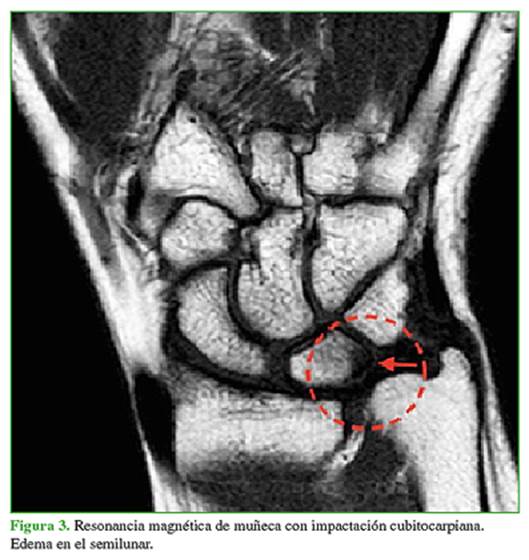

Este cuadro habitualmente se asocia a una varianza cubital positiva, ya sea congénita o adquirida. La varianza cubital se define como la diferencia de longitud relativa entre la esquina cubital de la fosa semilunar del radio y el punto más distal del domo de la cabeza cubital. Para realizar esta medición, en una radiografía anteroposterior de muñeca en rotación neutra, se trazan dos líneas perpendiculares al eje longitudinal del antebrazo, tangenciales al extremo proximal de la fosa semilunar del radio y al extremo distal de la superficie articular del domo del cúbito (Figura 1).9 Es positiva cuando el domo cubital está distal al borde medial de la fosa semilunar.8,10 El valor se expresa en milímetros y es independiente de la longitud de la apófisis estiloides cubital.8

Ante la sospecha de ICC, el primer estudio que se debe solicitar es una radiografía comparativa anteroposterior de muñeca. Se realiza con el hombro en abducción de 90º, el codo flexionado a 90º y el antebrazo en rotación neutra. También debe tomarse una radiografía de perfil y otra de frente en pronación máxima con fuerza de puño.8 Así se evalúa la varianza cubital tanto estática como dinámica.

Las radiografías características pueden mostrar esclerosis subcondral o cambios quísticos en el domo del cúbito, el borde posteromedial del semilunar o el borde posterolateral del piramidal.8 En casos severos, se puede observar una franca artrosis con formación osteofitaria en la articulación cubitocarpiana. Si se evalúa la posibilidad de realizar una osteotomía de acortamiento, también debe examinarse la articulación RCD y su inclinación anatómica. En el perfil, se debe buscar si hay una subluxación dorsal del cúbito.14